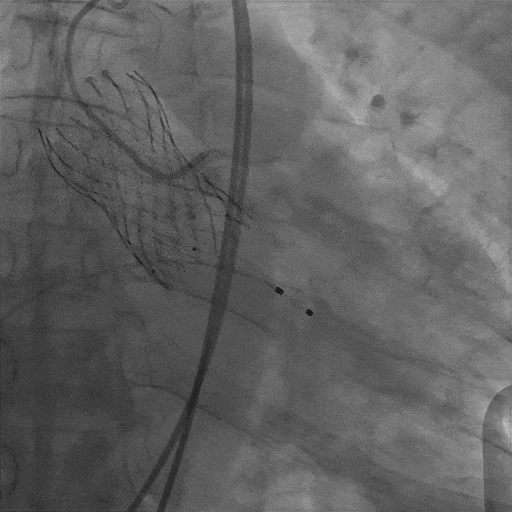

S3定位及植入

最终造影

(3)球扩瓣不同植入深度,将影响第一个瓣膜封堵区域(图8),本例患者在不影响二尖瓣前叶情况下,采用较深的植入深度:node 3-4之间(图9),最大限度规避冠脉堵塞风险,术后结果满意。